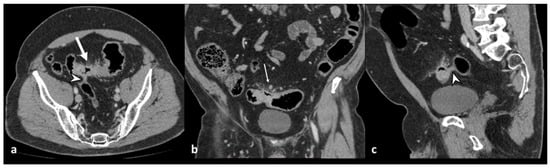

Figure 3. Axial unenhanced (a), axial and coronal contrast-enhanced CT images (b,c) show wall thickening of the left colon and inflammatory mass, without walls, located near the inflamed colonic tract, oval in shape, without an enhancing wall, that represents a peridiverticular phlegmon (arrowheads).

An increased density of pericolic fat [fat stranding] and a small amount of pericolic fluid represent the main mesenteric findings, which, combined with the mural thickening, suggest a localized inflammatory process in uncomplicated diverticulitis (Figure 2) [10,12,13]. The degree of fat stranding can range from “dirty fat” to peridiverticular phlegmon. The phlegmon consists of an inflammatory mass, without walls, located near the inflamed colonic tract, round or oval in shape, and on CT, it presents with high attenuation compared to the mesenteric fat, without an enhancing wall (Figure 3) [3,5]. Multiplanar reconstruction allows for identifying minimum amounts of pericolic fat stranding in the case of horizontal colonic segments [12]. Pereira et al. suggest that the presence of “disproportionate” fat stranding concerning mural thickening suggests the diagnosis of diverticulitis [21]. A small amount of fluid on the root of the mesentery [comma sign] and thickening of the lateroconal fascia are additional signs of an inflammatory process (Figure 1) [13].